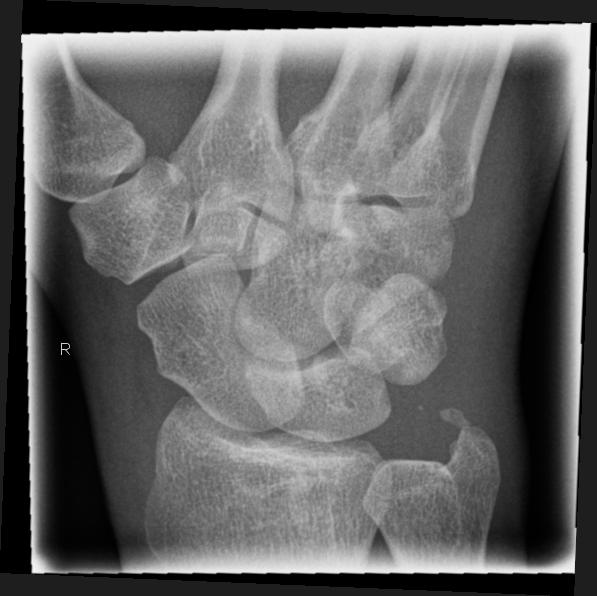

Scaphoid-Quartett

Indikation

Dringender Verdacht auf Scaphoidfraktur (2) bei zweifelhaften Befund in den Standardprojektionen.Notwendigkeit fraglich, da bei klinischen Verdacht und zweifelhaften Röntgenbefund in den Standardaufnahmen des Handgelenks ohnehin die Ruhigstellung indiziert ist, so dass sich eine weiterführende Diagnostik zunächst erübrigt. Ist auch die Kontrolluntersuchung nicht eindeutig, so sind CT oder Szintigraphie in ihrer Aussage zuverlässiger als die Spezialprojektionen.

Scaphoidfrakturen: 70% der Frakturen der Handwurzel sind Scaphoidfrakturen. 2/3 sind im mittleren Drittel. Meist Querfrakturen.

Dehizenz > 1mm -> instabil -> Gefahr Pseudarthrose.

Cave: Begleitverletzungen: Proc. syloideus radii, Lunatum, Capitatum, SL-Dissoziation, perilunäre Dissoziaton, DeQuervain Luxationsfraktur.